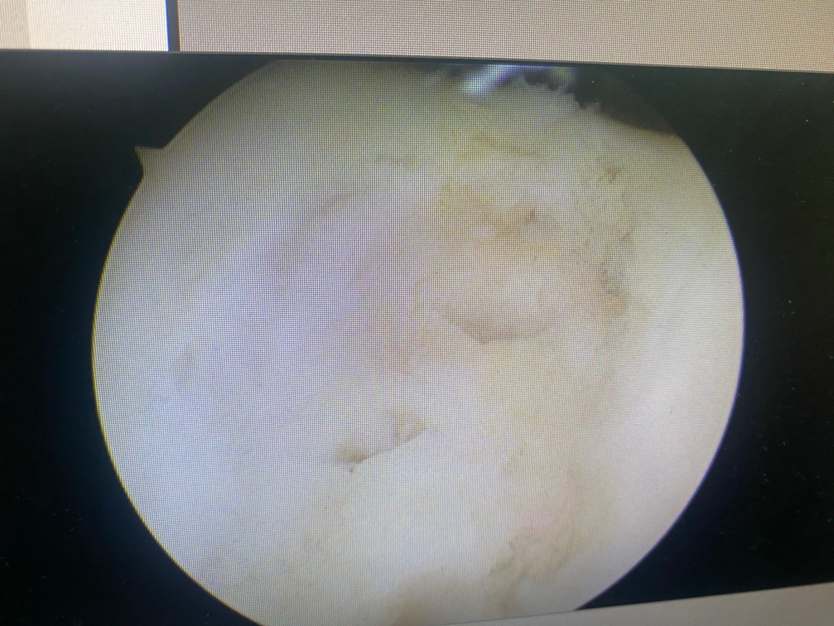

微骨折后骨髓骨细胞溢出